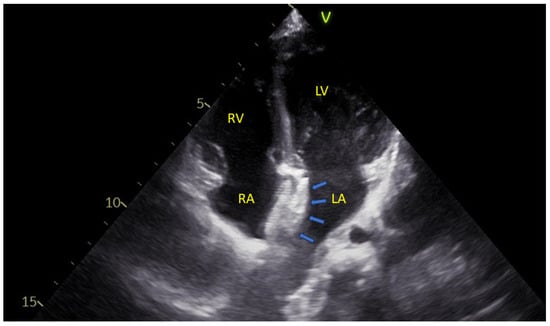

An example may be seen in Figure 2.

Figure 2. An apical four-chamber echocardiographic view showing the two disks of an atrial septal defect closure device (blue arrows) positioned within the interatrial septum. LA—Left Atrium; LV—Left Ventricle; RA—Right Atrium; RV—Right Ventricle.